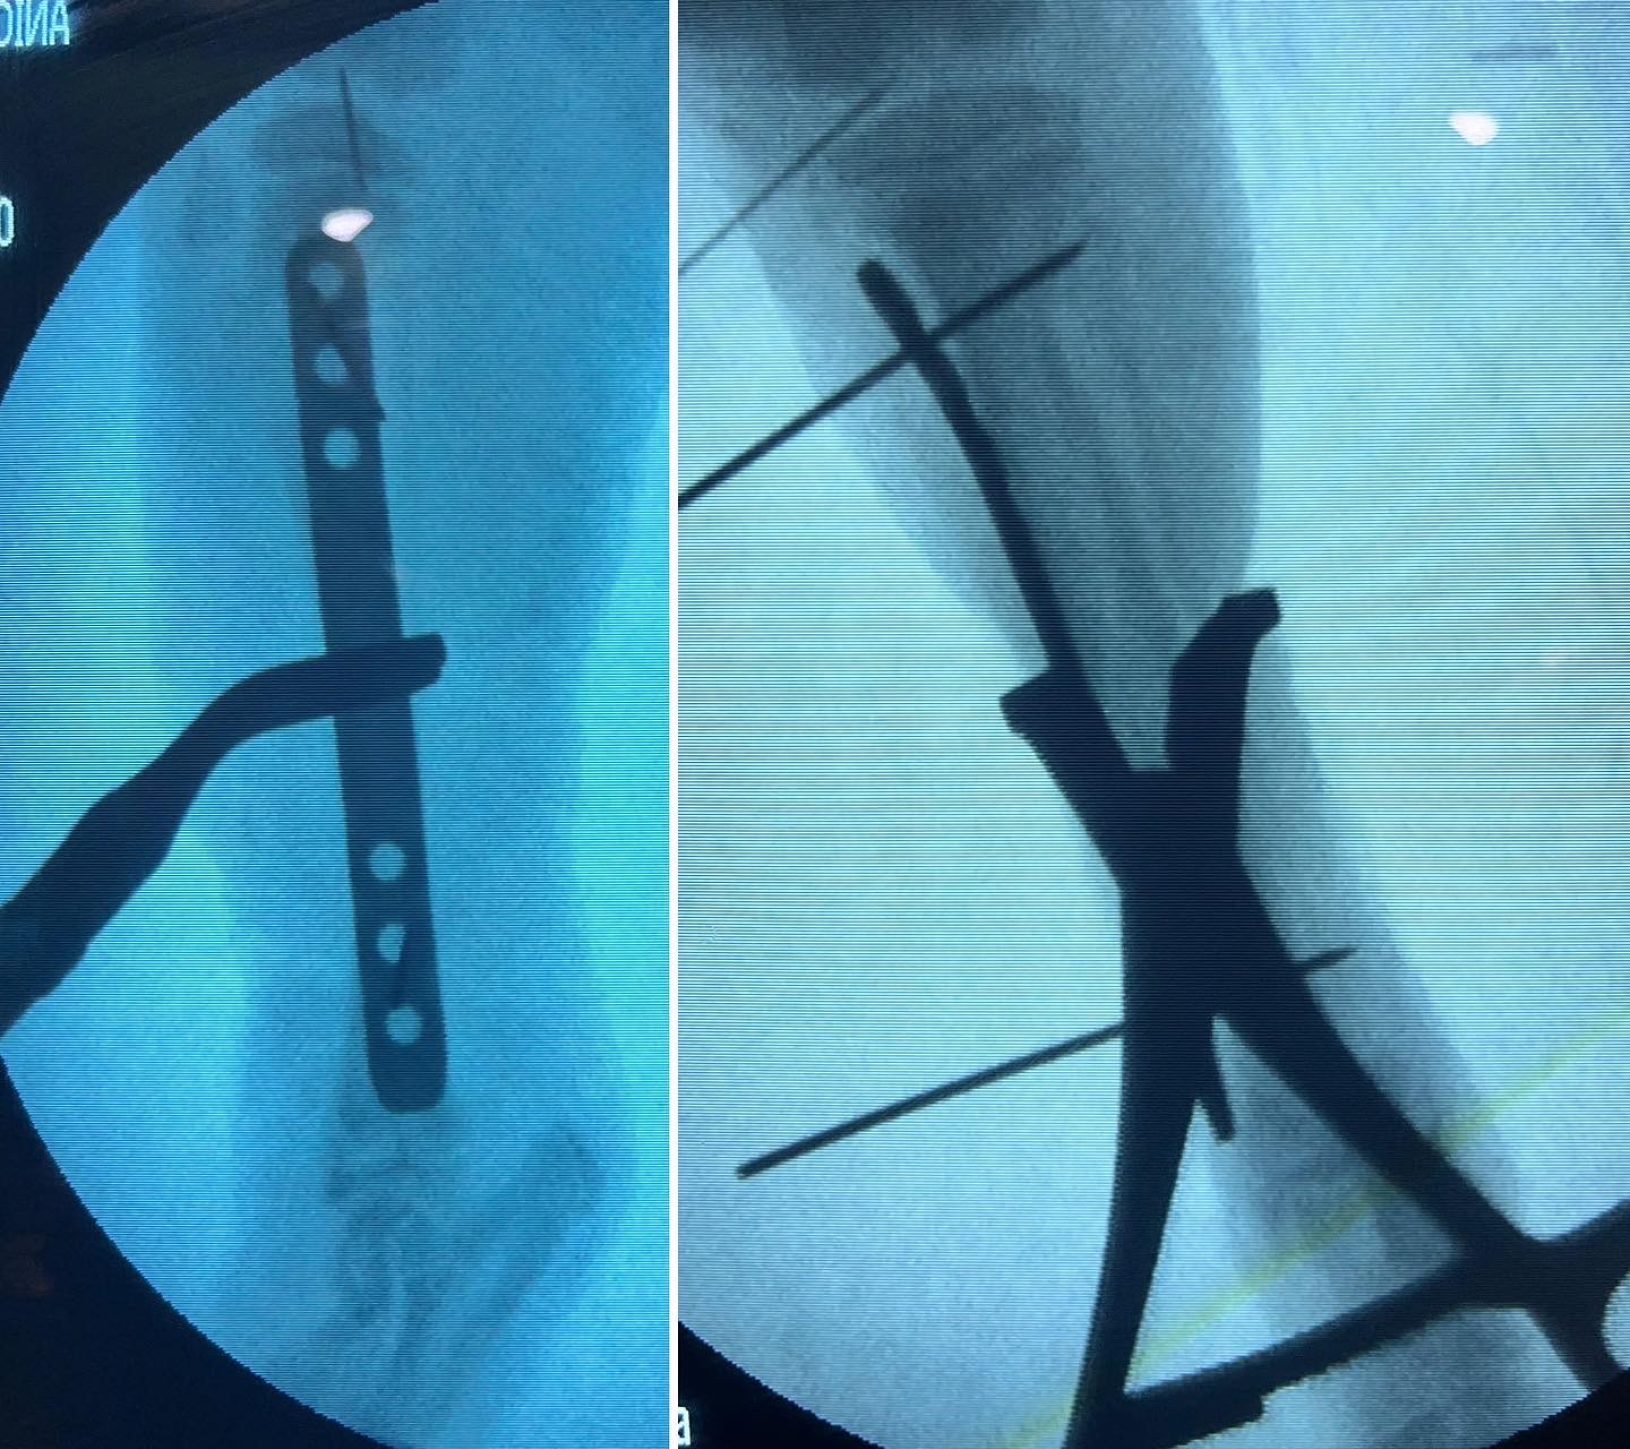

- Fijación externa: es una técnica que logra estabilizar los fragmentos de un hueso fracturado empleando dispositivos externos que se fijan al hueso mediante agujas que se insertan a través de la piel, conectándolas entre sí gracias a diferentes elementos.

- Minimally Invasive Plate Osteosynthesis (MIPO): minimiza la invasion quirúrgica al reducir la necesidad de grandes incisiones y abordajes pero requiere de una evaluación y planificación prequirúrgica exhaustiva. Generalmente se realizan pequeñas incisiones en los tejidos próximos a los fragmentos óseos a estabilizar, y se procede a la reducción de la fractura, idealmente asistida por un fluoroscopio que garantice el óptimo alineamiento óseo. Habituamente se premoldea una placa de osteosíntesis que se desliza a través de las pequeñas incisiones creadas sobre los fragmentos de hueso y se fija a los mismos utilizando tornillos. En último lugar se suturan las incisiones creadas. La menor agresión quirúrgica puede favorecer una recuperación mas rápida y predisponer a menos complicaciones postquirúrgicas. Sin embargo, no todas las fracturas se pueden manejar mediante esta técnica.